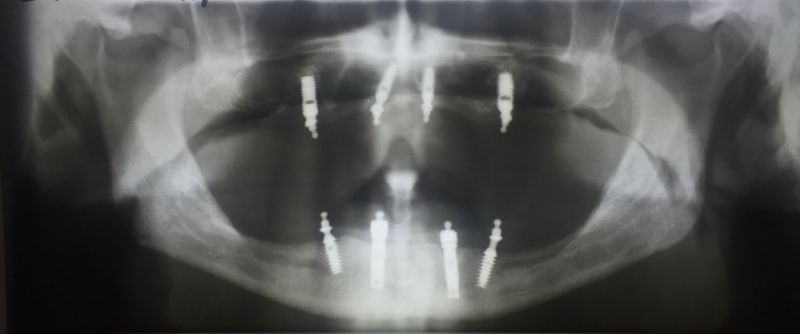

Viele Jahre haben die Implantate gehalten

Nun musste aber ein Implantat in regio 16 entfernt werden, wegen einer Periimplantitis.

Das Implantat und auch alle anderen wurden in 2003 gesetzt und war seitdem in Funktion. Alle anderen sind es immer noch! Seit inzwischen über 12 Jahren.

Das Schöne an der bestehenden Rekonstruktion: Das Implantat konnt entfertn werden, die vorhandene Prothese in der Zeit der Wundheilung weiterg etragen werden, auch als ein neues Implantat unter die bestehende Prothese neu inseriert wurde.

Diese neue Implantat wurde heute in der Praxis, man nennt es "chairside" in die bestehende Prothese eingebunden.